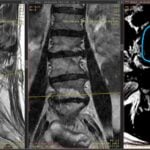

Infiltrațiile transforaminale sunt proceduri medicale minim invazive utilizate pentru diagnosticarea și tratamentul durerilor de spate și a altor afecțiuni legate de coloana vertebrală.

Aceste proceduri implică administrarea de medicamente, cum ar fi corticosteroizii și anestezicele, direct în spațiul în care se află nervii spinali, cunoscut sub numele de foramina.

- Evitarea chirurgiei: Pentru unii pacienți, tratamentul cu infiltrații transforaminale poate evita necesitatea unei intervenții chirurgicale. Aceste proceduri pot oferi o alternativă non-invazivă pentru a trata aceste dureri de spate.

- Evaluarea inițială: Înainte de a decide să efectuați infiltrații transforaminale, medicul va efectua o evaluare detaliată a stării dumneavoastră de sănătate și va discuta cu dumneavoastră despre simptomele și istoricul durerii.